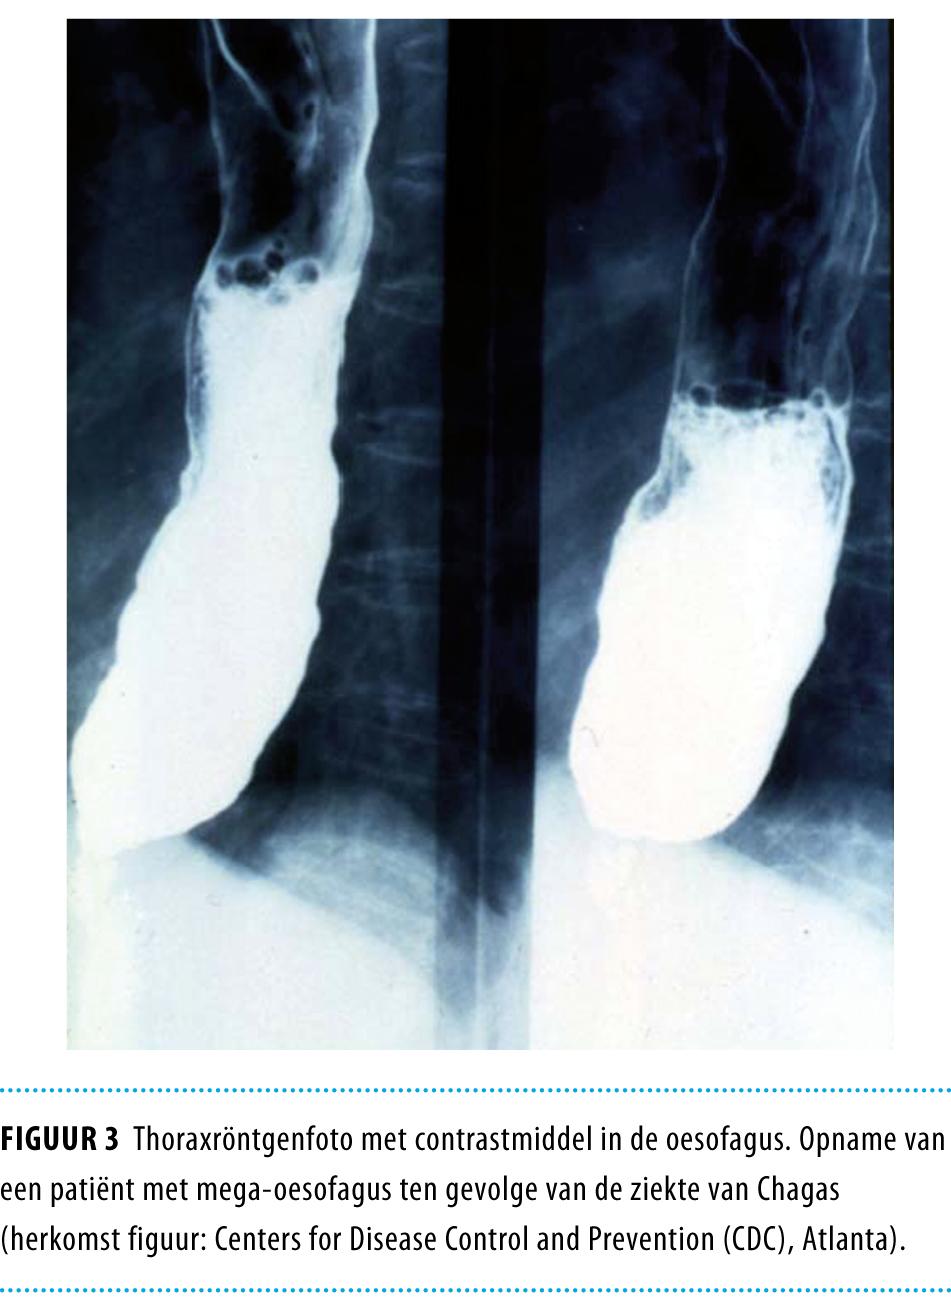

Bij 10-15% van de chronisch geïnfecteerden treden gastro-intestinale afwijkingen op.1 Door progressieve schade aan autonome zenuwcellen kunnen motiliteitsstoornissen en uiteindelijk mega-oesofagus en megacolon ontstaan (figuur 3).10 De slokdarmafwijkingen bij de ziekte van Chagas onderscheiden zich niet van die bij idiopathische achalasie. Ook de colonafwijkingen bij de ziekte van Chagas zijn niet specifiek.

Figuur 3